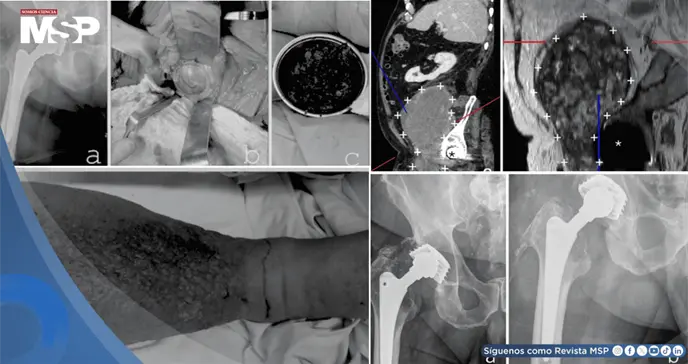

Al analizar las imágenes con más detalle, se observó una relación anatómica muy estrecha entre la masa "tumoral" y la antigua articulación de la cadera protésica. Esto hizo reconsiderar el diagnóstico.

Se realizó una punción de la cadera, cuyos resultados no fueron concluyentes, en parte por la posible interferencia de los residuos metálicos. Frente a la sospecha de que se trataba de una reacción adversa local al desgaste de la prótesis (una complicación conocida pero poco frecuente que puede formar masas o pseudotumores), y no de un cáncer, los médicos decidieron intervenir.

La cirugía se realizó con dos equipos: uno para extirpar la masa principal (dejando un pequeño resto por seguridad, al estar adherida a vasos) y otro para revisar la prótesis de cadera. El análisis inmediato de la masa durante la operación no mostró células cancerosas.

Dentro de la articulación, se encontraron signos de corrosión en la unión de la cabeza metálica con el vástago. Dado que el vástago principal estaba bien fijado al hueso, lo preservaron, pero reemplazaron toda la parte acetabular (la copa) y la cabeza femoral por componentes modernos de cerámica y polietileno especial para mayor durabilidad.

El estudio definitivo del tejido extirpado confirmó que era un seudotumor: una masa formada por una reacción inflamatoria crónica a partículas microscópicas de metal y plástico del desgaste de la prótesis, mezclada con sangre antigua organizada.

No había tumor maligno. Tras la cirugía, la hinchazón de la pierna mejoró notablemente al liberarse la compresión vascular. Sin embargo, se identificó una infección profunda de la prótesis por una bacteria resistente (SARM), que no se había detectado en las pruebas previas.